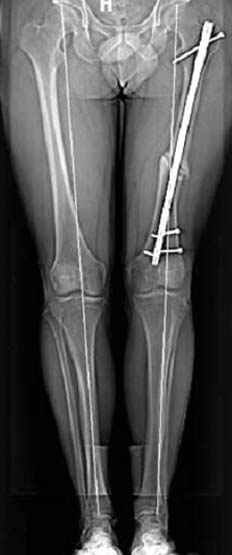

Несколько снимков из моей коллекции, чтобы разьяснить, почему мы до сих пор делаем различные варианты остеотомии.

На рисунке N1 предоперационный план лечения ложного сустава шейки бедра- линия ложного сустава, угол и направление введения импланта, клиновидная остеотомия в градусах и миллиметрах, второй снимок после коррекции, расчет, на сколько удлиняется конечность и размеры импланта;

N3 рисунок окончательный снимок, после операции моя рентгенограмма должен выглядеть примерно как эта картина. На N4 снимке клин перед удалением; N5 послеоперации 3 нед.; N6 окончательная рентгенограмма.